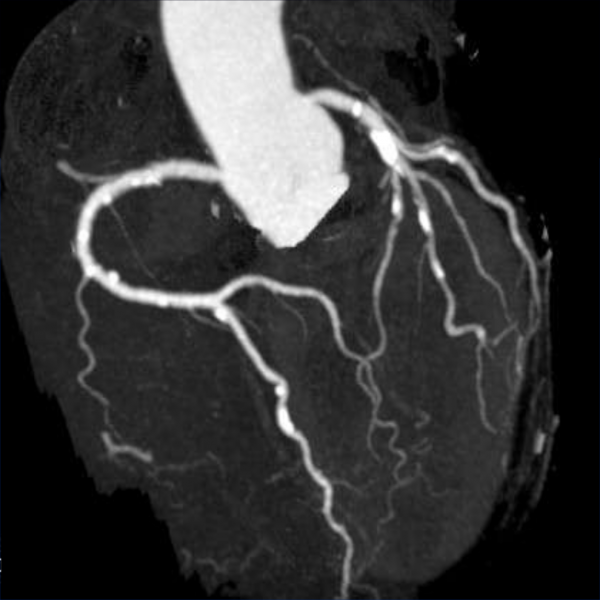

Coroscanner avec injection: permet quoi ?

A

. détecte les sténoses coronariennes

. visualise l’anatomie coronaire sans renseignement sur le caractère fonctionnel

. très bonne VPN

. mais mauvaise VPP